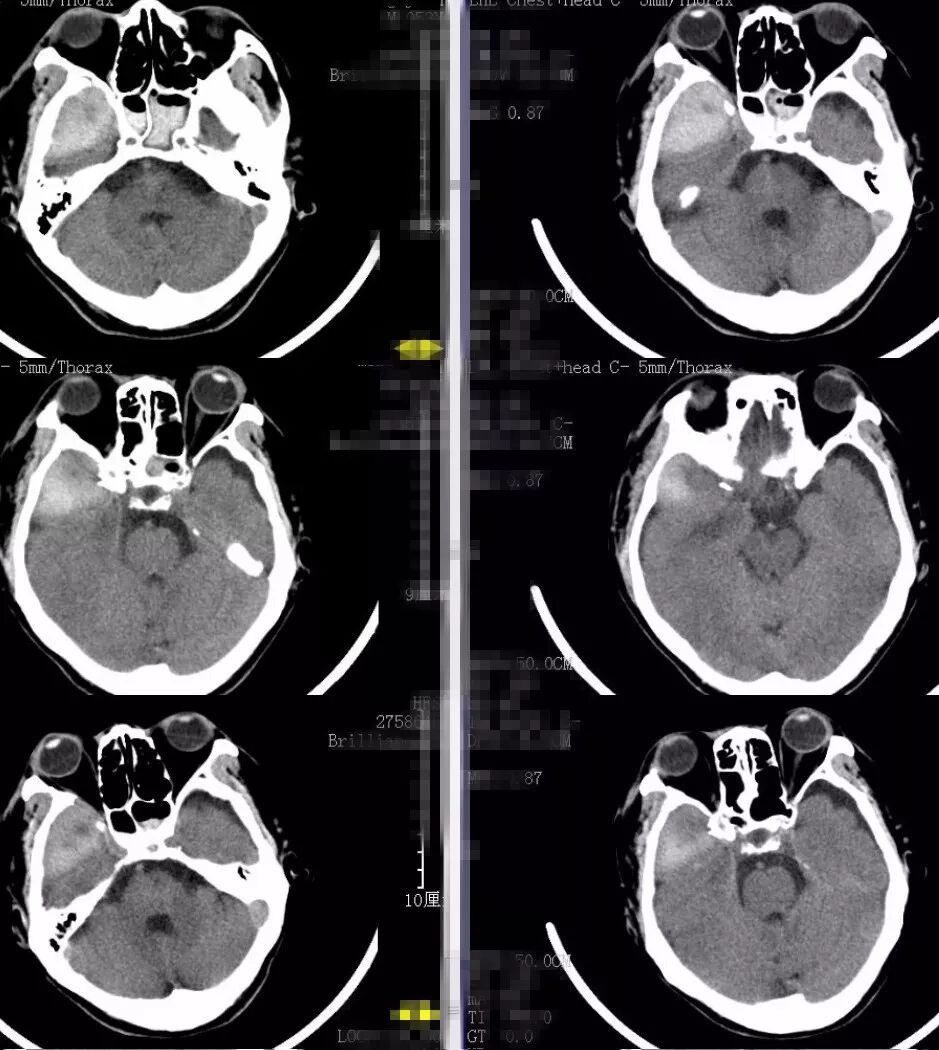

辅助检查:2018-1-10复查头部及胸部CT:右颞部硬膜外血肿。右侧颞骨、颧弓骨折,右侧颅底多发骨折(图1)。右侧液气胸,胸腔引流管在位。右侧多发肋骨骨折。右肱骨正侧位片:右侧肱骨下端粉碎性骨折。

图1. 2018-1-10入院时头CT:右颞部硬膜外大血肿。右侧颞骨、颧弓骨折,右侧颅底多发骨折。